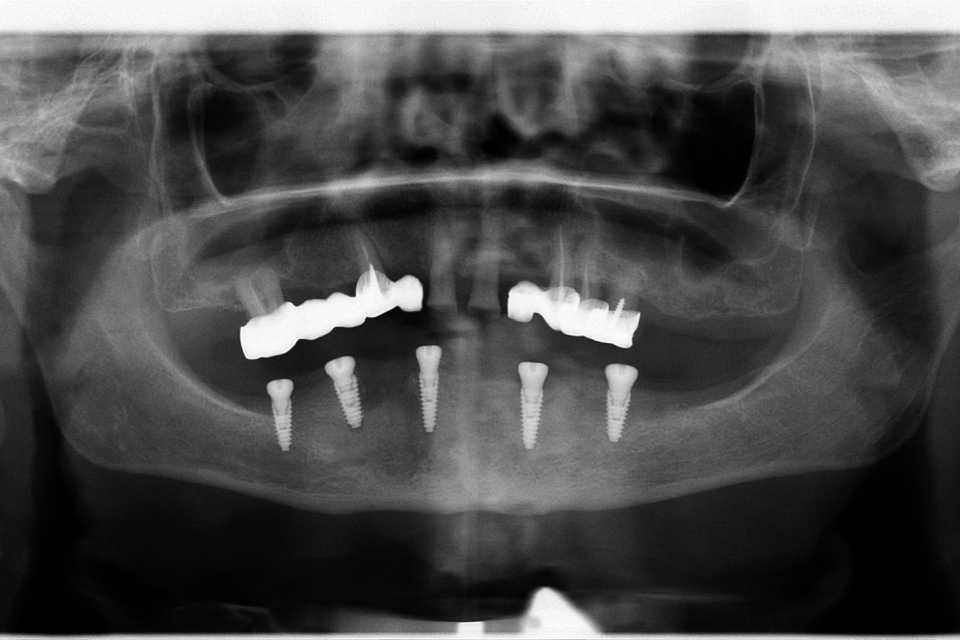

Pacienta, în vârstă de 65 de ani, se prezintă în cabinet acuzând dureri în timpul masticației, mobilitate dentară, halitoză și un aspect inestetic.

Planul de tratament a inclus extracția dinților parodontotici la nivelul mandibulei și inserarea a 5 implanturi dentare Mega-Gen AnyRidge cu conexiune multiunit, urmată de protezarea acestora cu o lucrare fixă, înșurubabilă, din ceramică pe suport de zirconiu.

La nivelul maxilarului, s-au efectuat extracțiile dinților parodontotici, tratamentul laser și chirurgical al leziunilor parodontale, urmate de reabilitarea protetică prin realizarea a două lucrări fixe din ceramică pe suport de zirconiu.